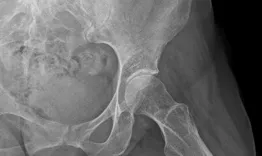

A 24-year-old female patient presents with hip pain. Pre-op X-rays reveal total lysis of the shelf: What causes the patient's symptoms and how would you manage this condition? The goals of this clinical case are to discuss the different indications and therapeutic options for a hip dysplasia in a young patient, as well as possible complications.

Hip dysplasia in a young woman: How should I treat?

Nicolas Reina